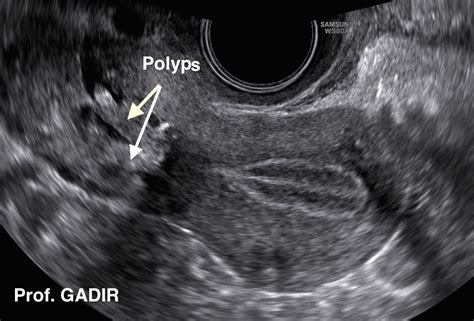

These polyps typically range from a few millimeters to 2 centimeters in length, and can appear in various colors including reddish-pink, purple, or grayish-white. They often have a bulb-like shape with a thin stem, resembling small, delicate fingers protruding from the cervix.

Cervical polyps are typically discovered during routine pelvic examinations or Pap smear tests. Healthcare providers use a speculum to visualize the cervix and can often identify these growths during a standard gynecological checkup. If a polyp is detected, a biopsy is usually performed to rule out any potential cancerous changes.